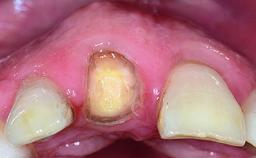

A healthy 37-year-old female patient was referred for a consultation on the replacement of missing tooth 21 with an implant-supported restoration. She stated that several years previously the tooth had been traumatically avulsed following a motor vehicle accident. The tooth was replaced with a three-unit fixed partial denture (FPD) immediately afterwards. Over time, she became disillusioned with the FPD and looked for a different option, including orthodontic therapy. She presented still in her orthodontic appliances, with the pontic sectioned free from the FPD but attached to the archwire. Her orthodontist felt that orthodontic treatment had been successfully completed, but nevertheless referred her before removing the appliances in case adjustments were necessary.

Bone Volume Deficient horizontally, allowing simultaneous augumentation

Soft Tissue Contour and Volume Slightly compromised